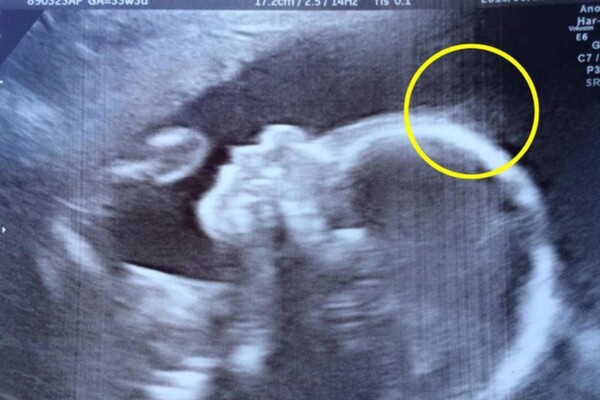

Cũng giống như rất nhiều bà bầu khác, chị Natasha Gent, 28 tuổi, đến từ thành phố Medway, hạt Kent, phía Đông Nam nước Anh, cũng đi khám định kỳ. Tuy nhiên, khi đến viện để siêu âm ở tuần thứ 20, chị Natasha đã được bác sĩ thông báo về một điều đặc biệt, điểm lạ trên cơ thể con gái khiến chị không khỏi hoang mang, lo lắng.

Hình ảnh siêu âm cho thấy ở trán của em bé có rất nhiều sợi như tóc lởm chởm ở trên, điều này rất ít khi thấy ở những đứa trẻ khác. Nghe bác sĩ kết luận, ban đầu, chị Natasha và gia đình không khỏi hoảng sợ vì nghĩ có thể con đang mắc bệnh gì đó.